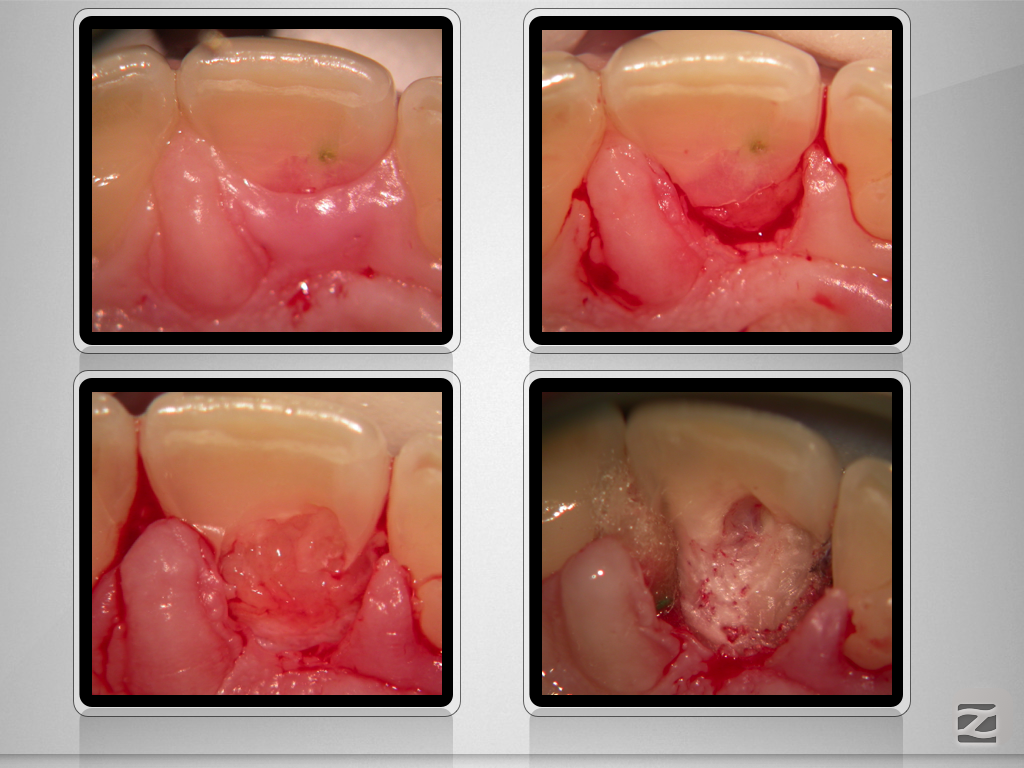

Back to the Future